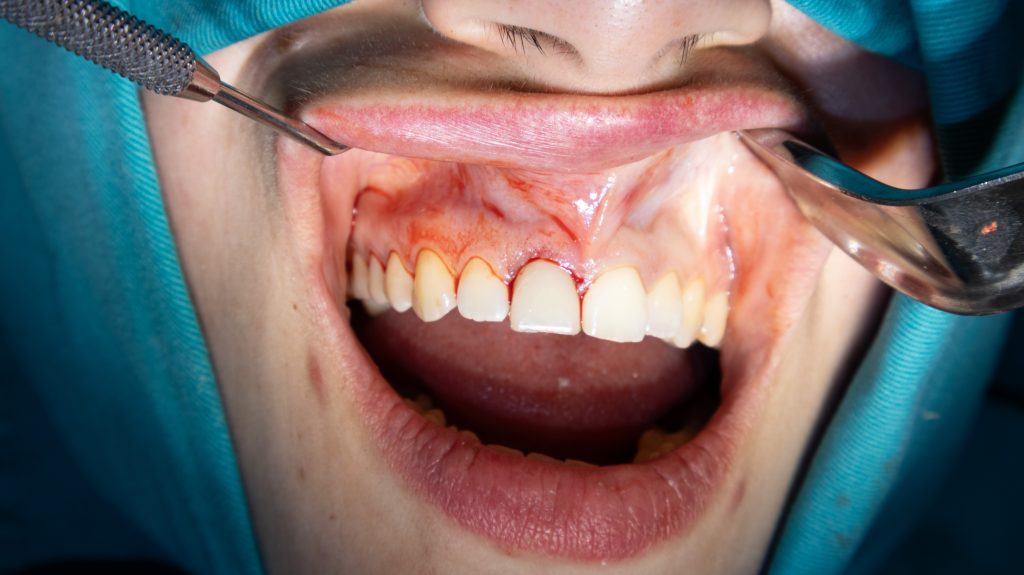

Surgical stage